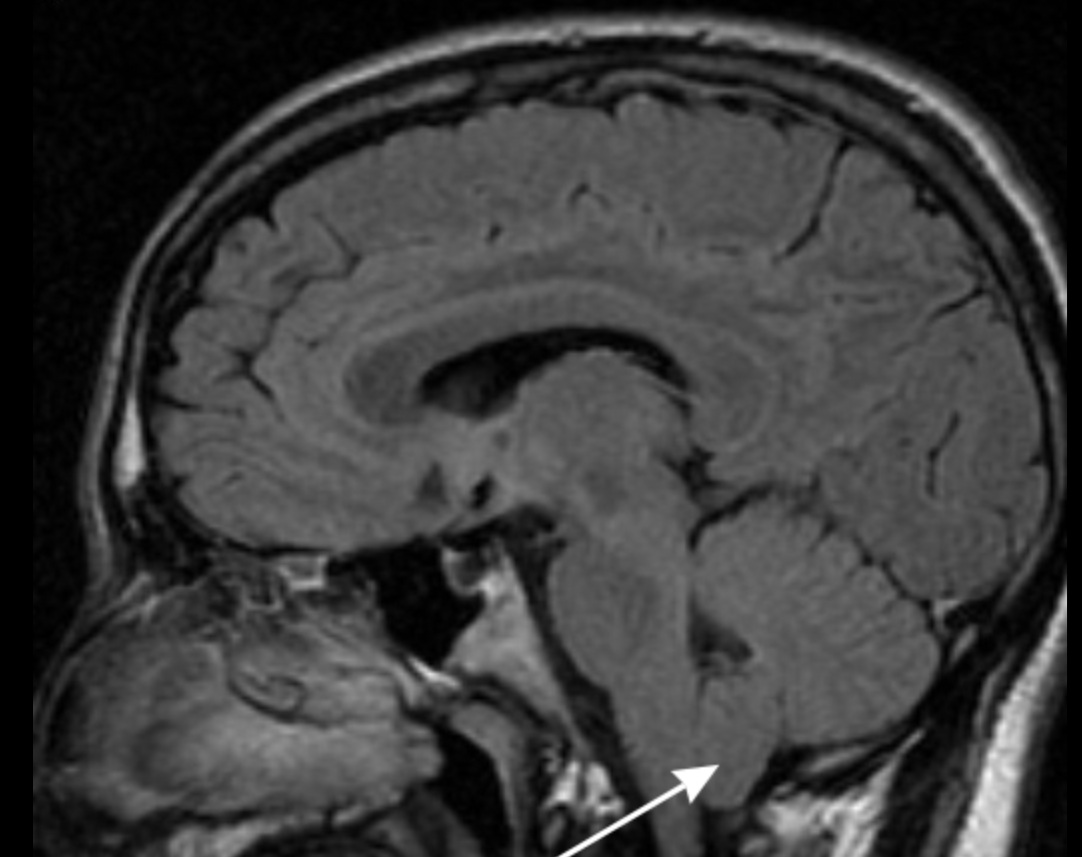

Evaluación de compresión cervicomedular y decisión de descompresión posterior.

Correlación clínico-radiológica y decisión de descompresión según síntomas y hallazgos.

Neurocirujano formado en la Universidad de Santiago de Chile (USACH), con especial cercanía a la patología de columna y al neurotrauma. Enfoque centrado en el bienestar integral del paciente, combinando criterios clínicos, neuroimagen y práctica basada en evidencia.